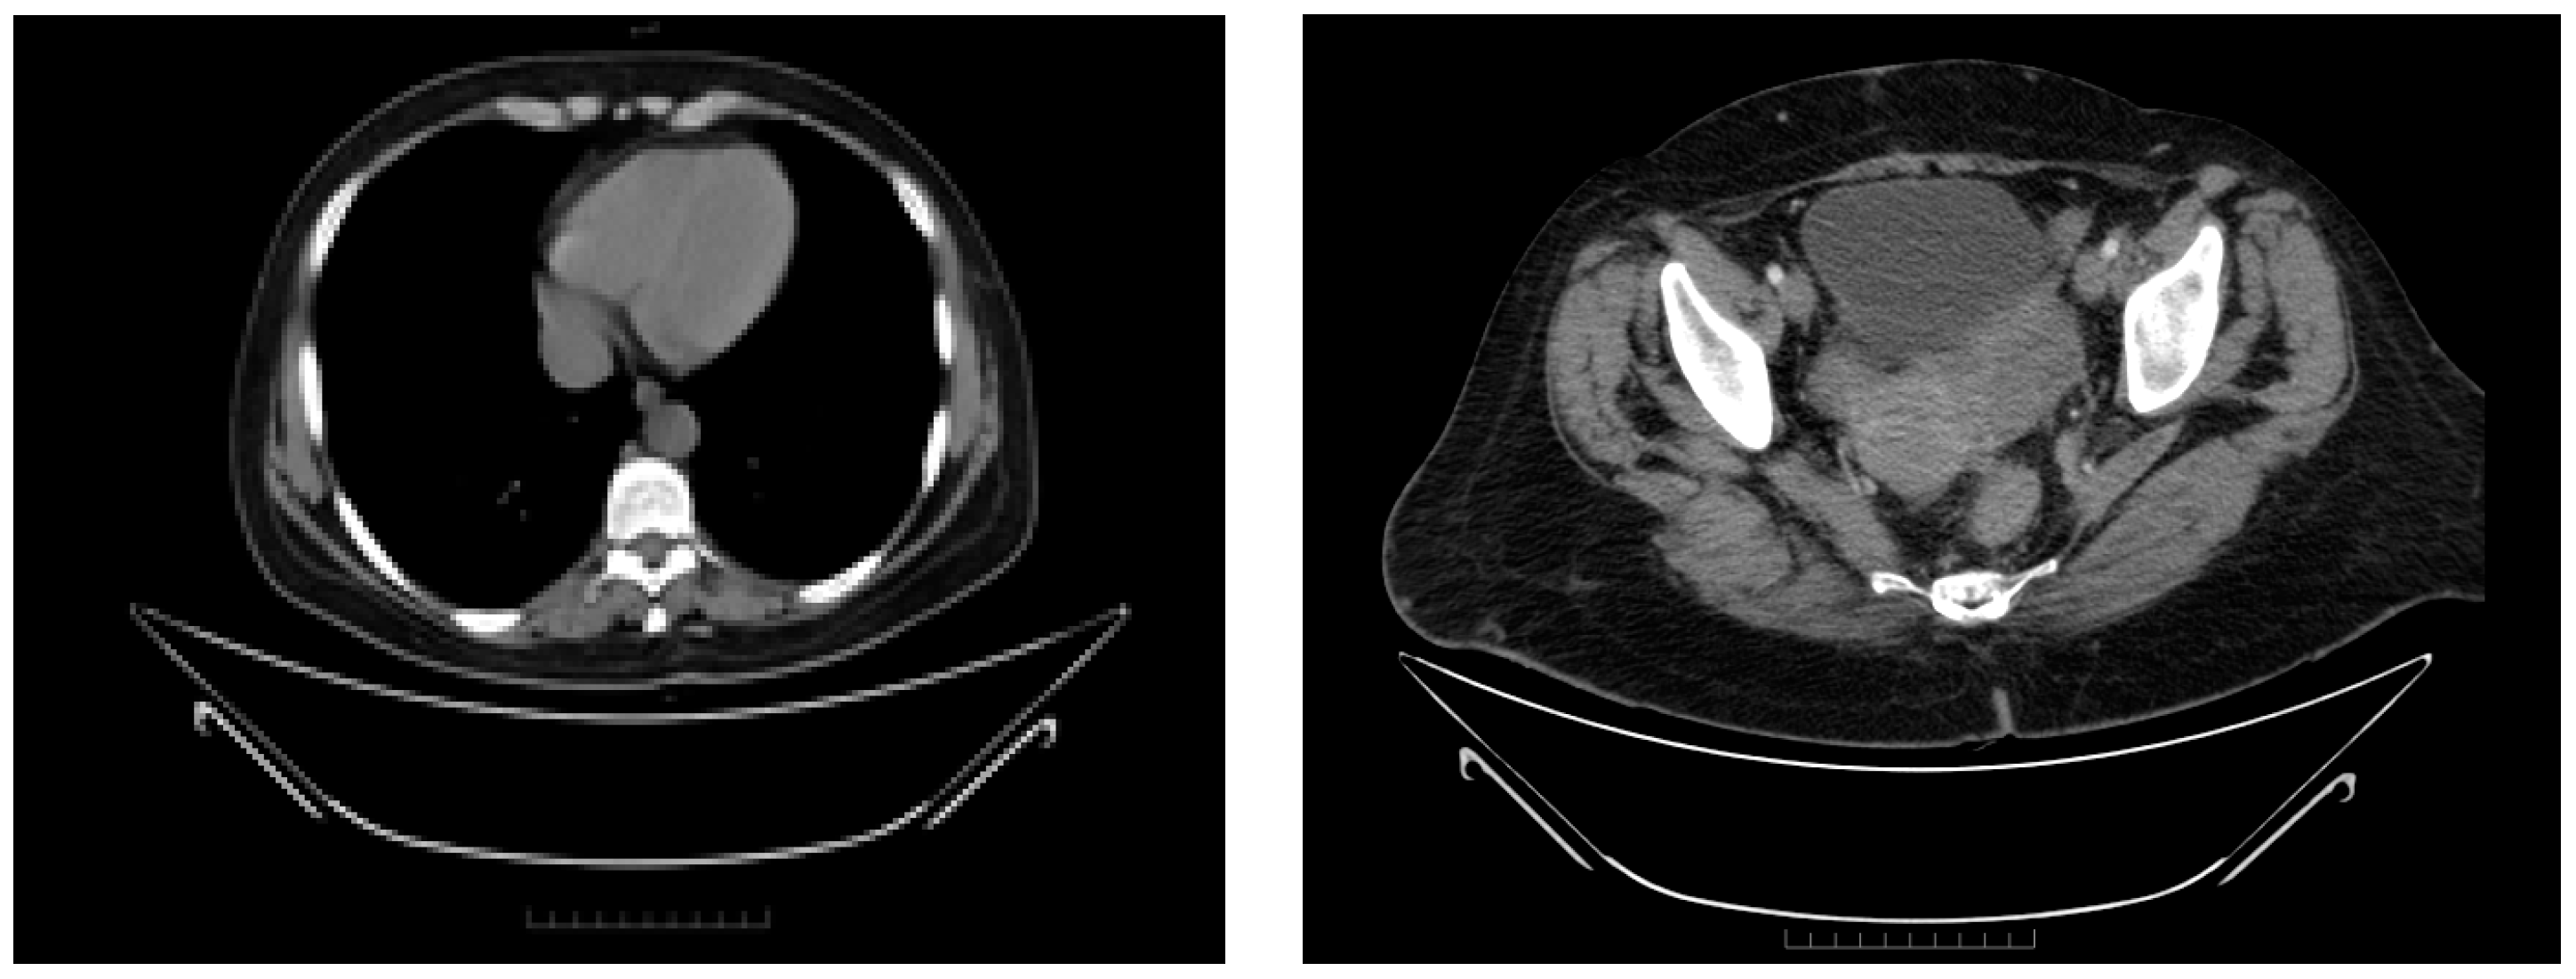

Between September 2015 and February 2016, six cycles of Carboplatin (AUC 5) and Paclitaxel (175 mg/m2) were administered every 3 weeks, with good clinical tolerance and without hematological toxicity. A post-chemotherapy CT scan described a partial response according to RECIST 1.1. The CT imaging findings revealed a significant change in the patient’s tumoral burden, demonstrating a left adnexal tumor measuring 75/56 mm with malignant features and indistinct boundaries from the uterine fundus, suggesting direct invasion or close association. In a positive turn of events, the previously noted pleural effusion had resolved, and there was a complete disappearance of ascitic fluid, indicating a favorable response to the recent therapeutic intervention (Figure 8). After six cycles of chemotherapy, the CA-125 level was 9.04 IU/L.

Figure 8.

The first follow-up (CT scan of the thorax and pelvis, March 2016) showing partial response to treatment.